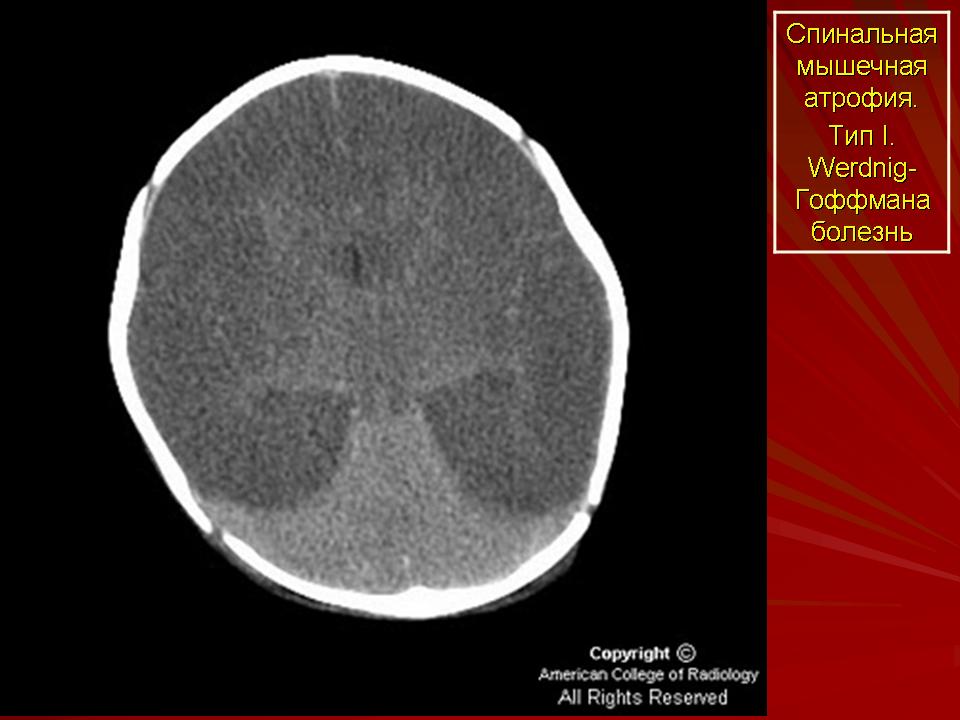

СAМ I (болезнь Верднига-Гоффмана, OMIM*253300) - наиболее тяжелая форма, первые симптомы можно нередко выявить еще во внутриутробном периоде по слабому шевелению плода. У значительного числа больных этой формой отчетливые клинические проявления отмечаются до 6-ти месячного возраста и характеризуются выраженными признаками вялого паралича мышц конечностей и туловища, с вовлечением в процесс дыхательной мускулатуры. Дети не держат голову, не сидят самостоятельно.

Проксимальная спинальная амиотрофия I, II III типа (САМ I-III) - одно из наиболее частых наследственных заболеваний с аутосомно-рецессивным типом наследования, с частотой встречаемости 1 на 6000-10000 новорожденных. Основной механизм развития клинических признаков связан с прогрессирующей дегенерацией мотонейронов передних рогов спинного мозга, что выражается в атрофии проксимальных мышц конечностей, в первую очередь.

Выделяют три формы заболевания на основе возраста начала, тяжести течения и продолжительности жизни.